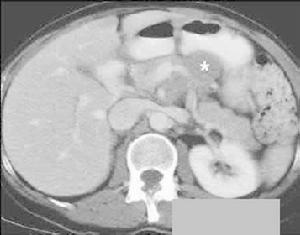

胰腺囊性病變2、這項工作有三十多年的歷史,最初的系統有三個柜子那么大。